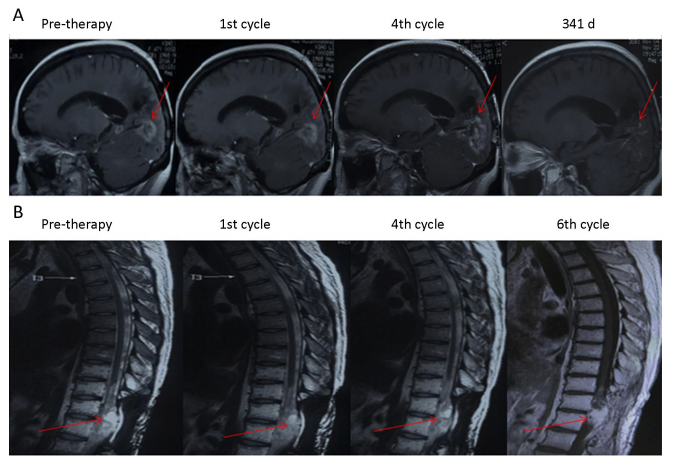

1、研究發(fā)現(xiàn),綠原酸治療對部分患者(P3P4)有效,使腫瘤病灶縮小,達(dá)到穩(wěn)定疾病狀態(tài)(SD)。P3P4的無進(jìn)展生存期(PFS)分別為8.1個月和4.9個月,總生存期(OS)均超過16.5個月,且至今仍存活。

P3和P4患者綠原酸治療前后的磁共振成像(MRI)圖像